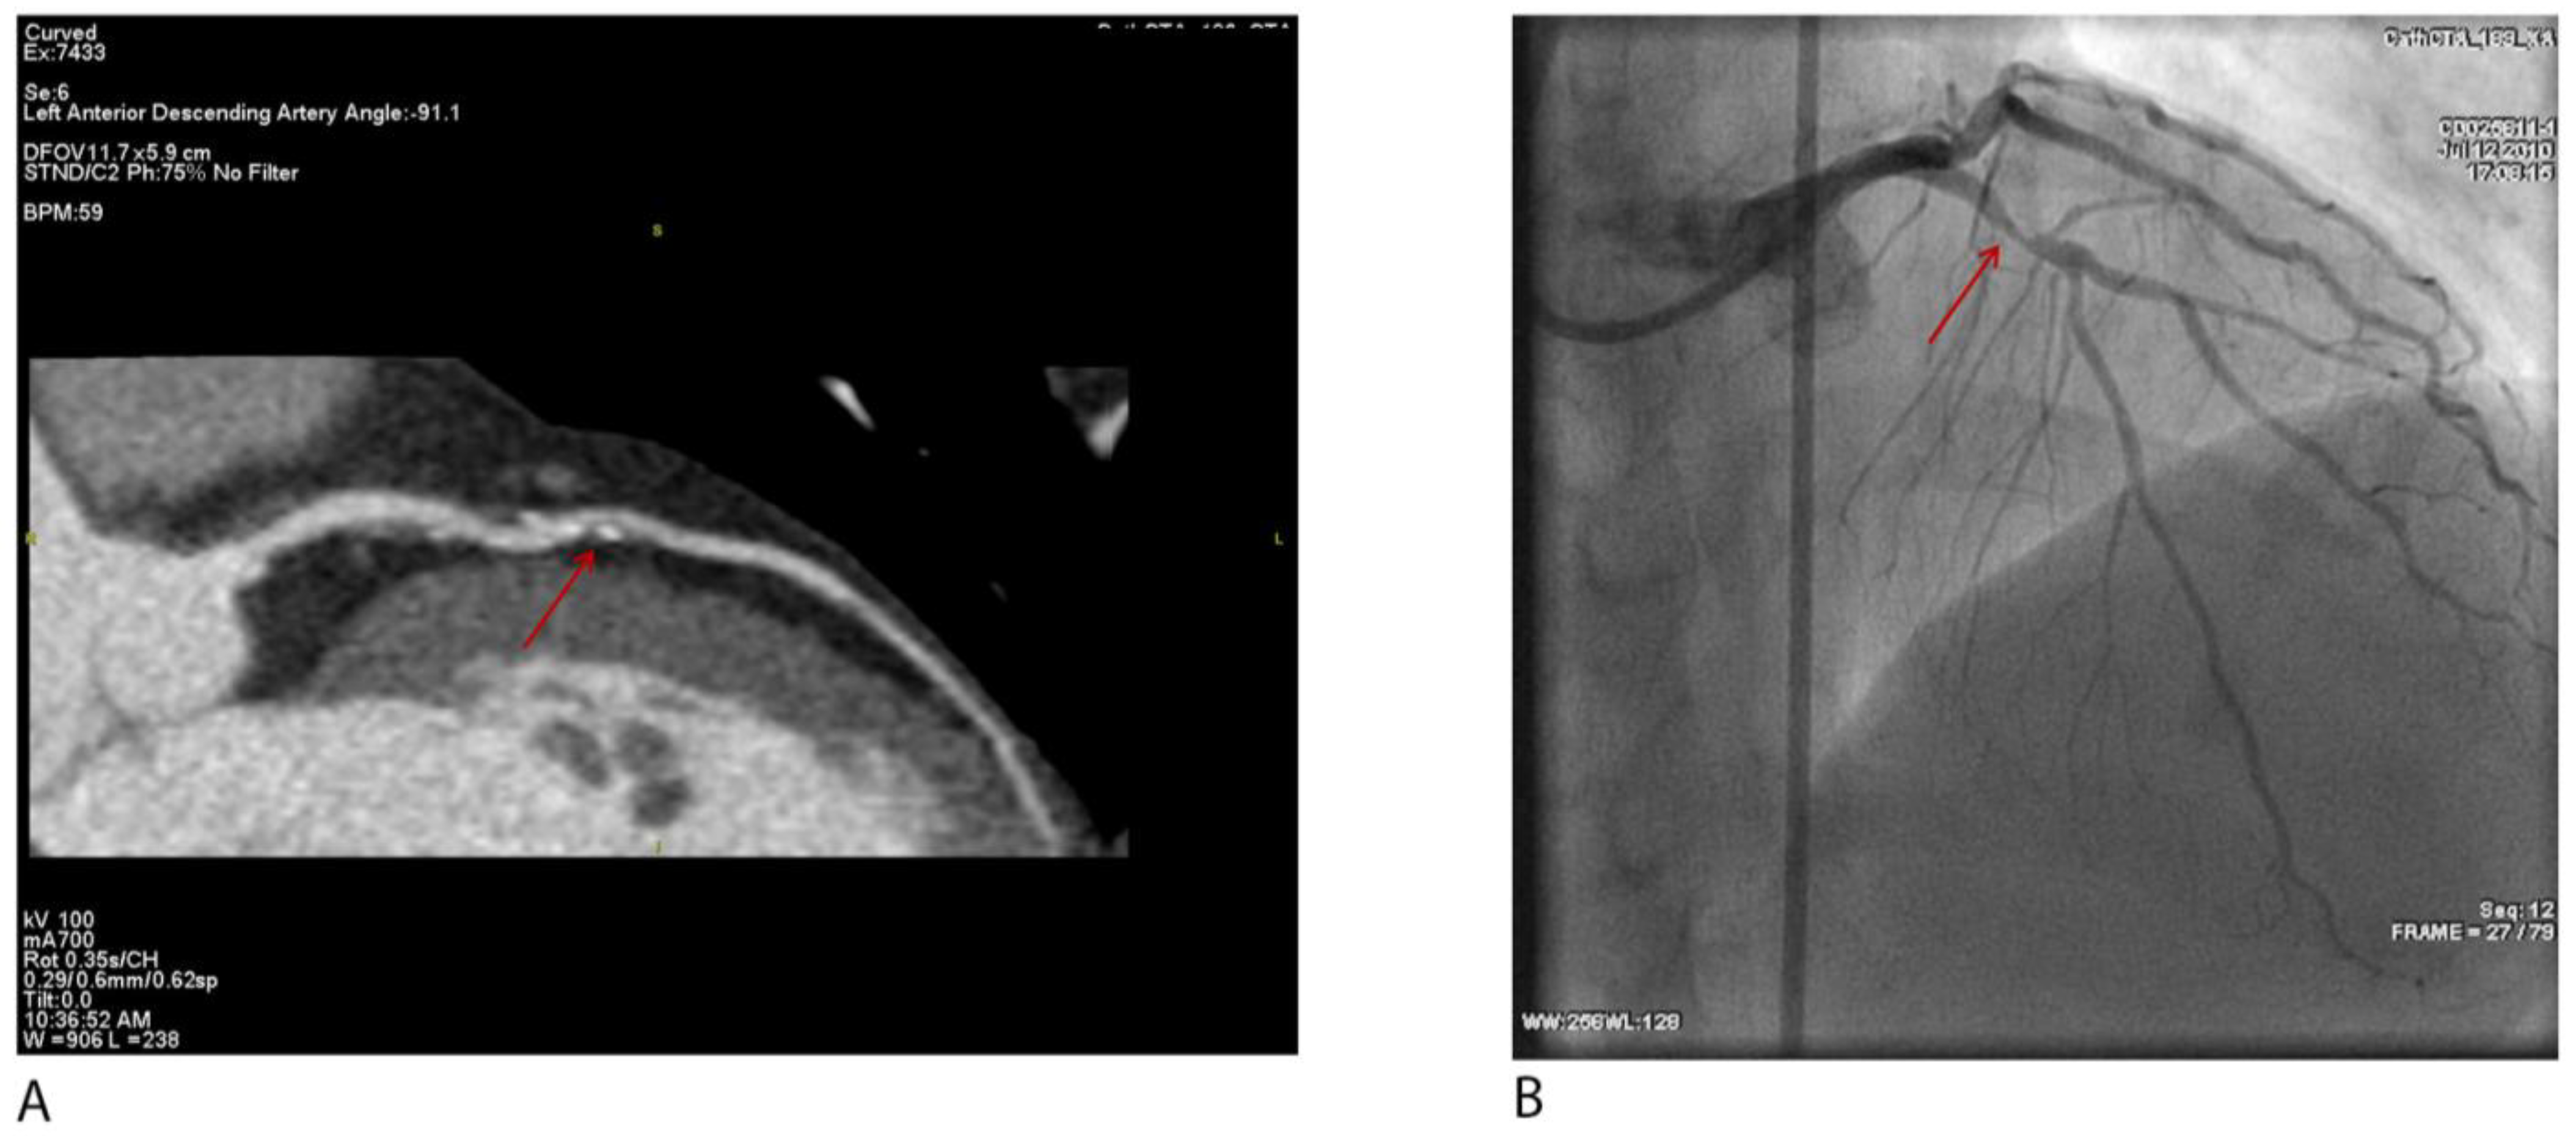

As demonstrated in Figure 3A,B, curved planar CCTA clearly visualizes a severe focal stenosis in the mid-LAD, confirmed by selective coronary angiography. This highlights CCTA’s excellent correlation with invasive gold standards.

Figure 3.

(A) Curved planar reformatted coronary CT angiography (CCTA) demonstrates a severe (>70%) focal stenosis in the mid left anterior descending artery (LAD), characterized by mixed plaque with both non-calcified and calcified components, as well as eccentric calcification. The red arrow points to a severe (>70%) focal stenosis in the mid LAD. (B) Invasive coronary angiography of the same patient confirms the presence of a severe stenosis in the mid-LAD (arrow).